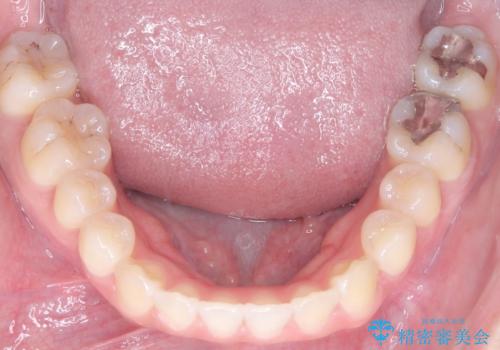

- 患者様は、上の前歯に翼状捻転(歯が回転して生えている状態)があり、全体の歯並び(叢生)の改善を希望して来院されました。診断の結果、非抜歯での治療が可能であると判断し、上顎にリンガルアーチを装着し、矯正用アンカースクリューを併用することで臼歯部を確実に遠心移動させる治療計画を立案しました。これにより、スペースを確保しつつ、前歯をきれいに並べることを目指しました。

治療では、審美ワイヤーを使用し、目立ちにくく配慮しながら矯正を進めました。上顎にリンガルアーチと矯正用アンカースクリューを用いて臼歯部を安定的に遠心移動させ、歯列全体のスペースを確保しました。その後、回転していた前歯を正しい位置に配列し、全体的な歯並びの改善を行いました。治療中は、装置の適切な管理と口腔衛生を徹底することが重要でした。結果として、見た目だけでなく機能的にも優れた歯列を実現することができ、患者様にもご満足いただけました。